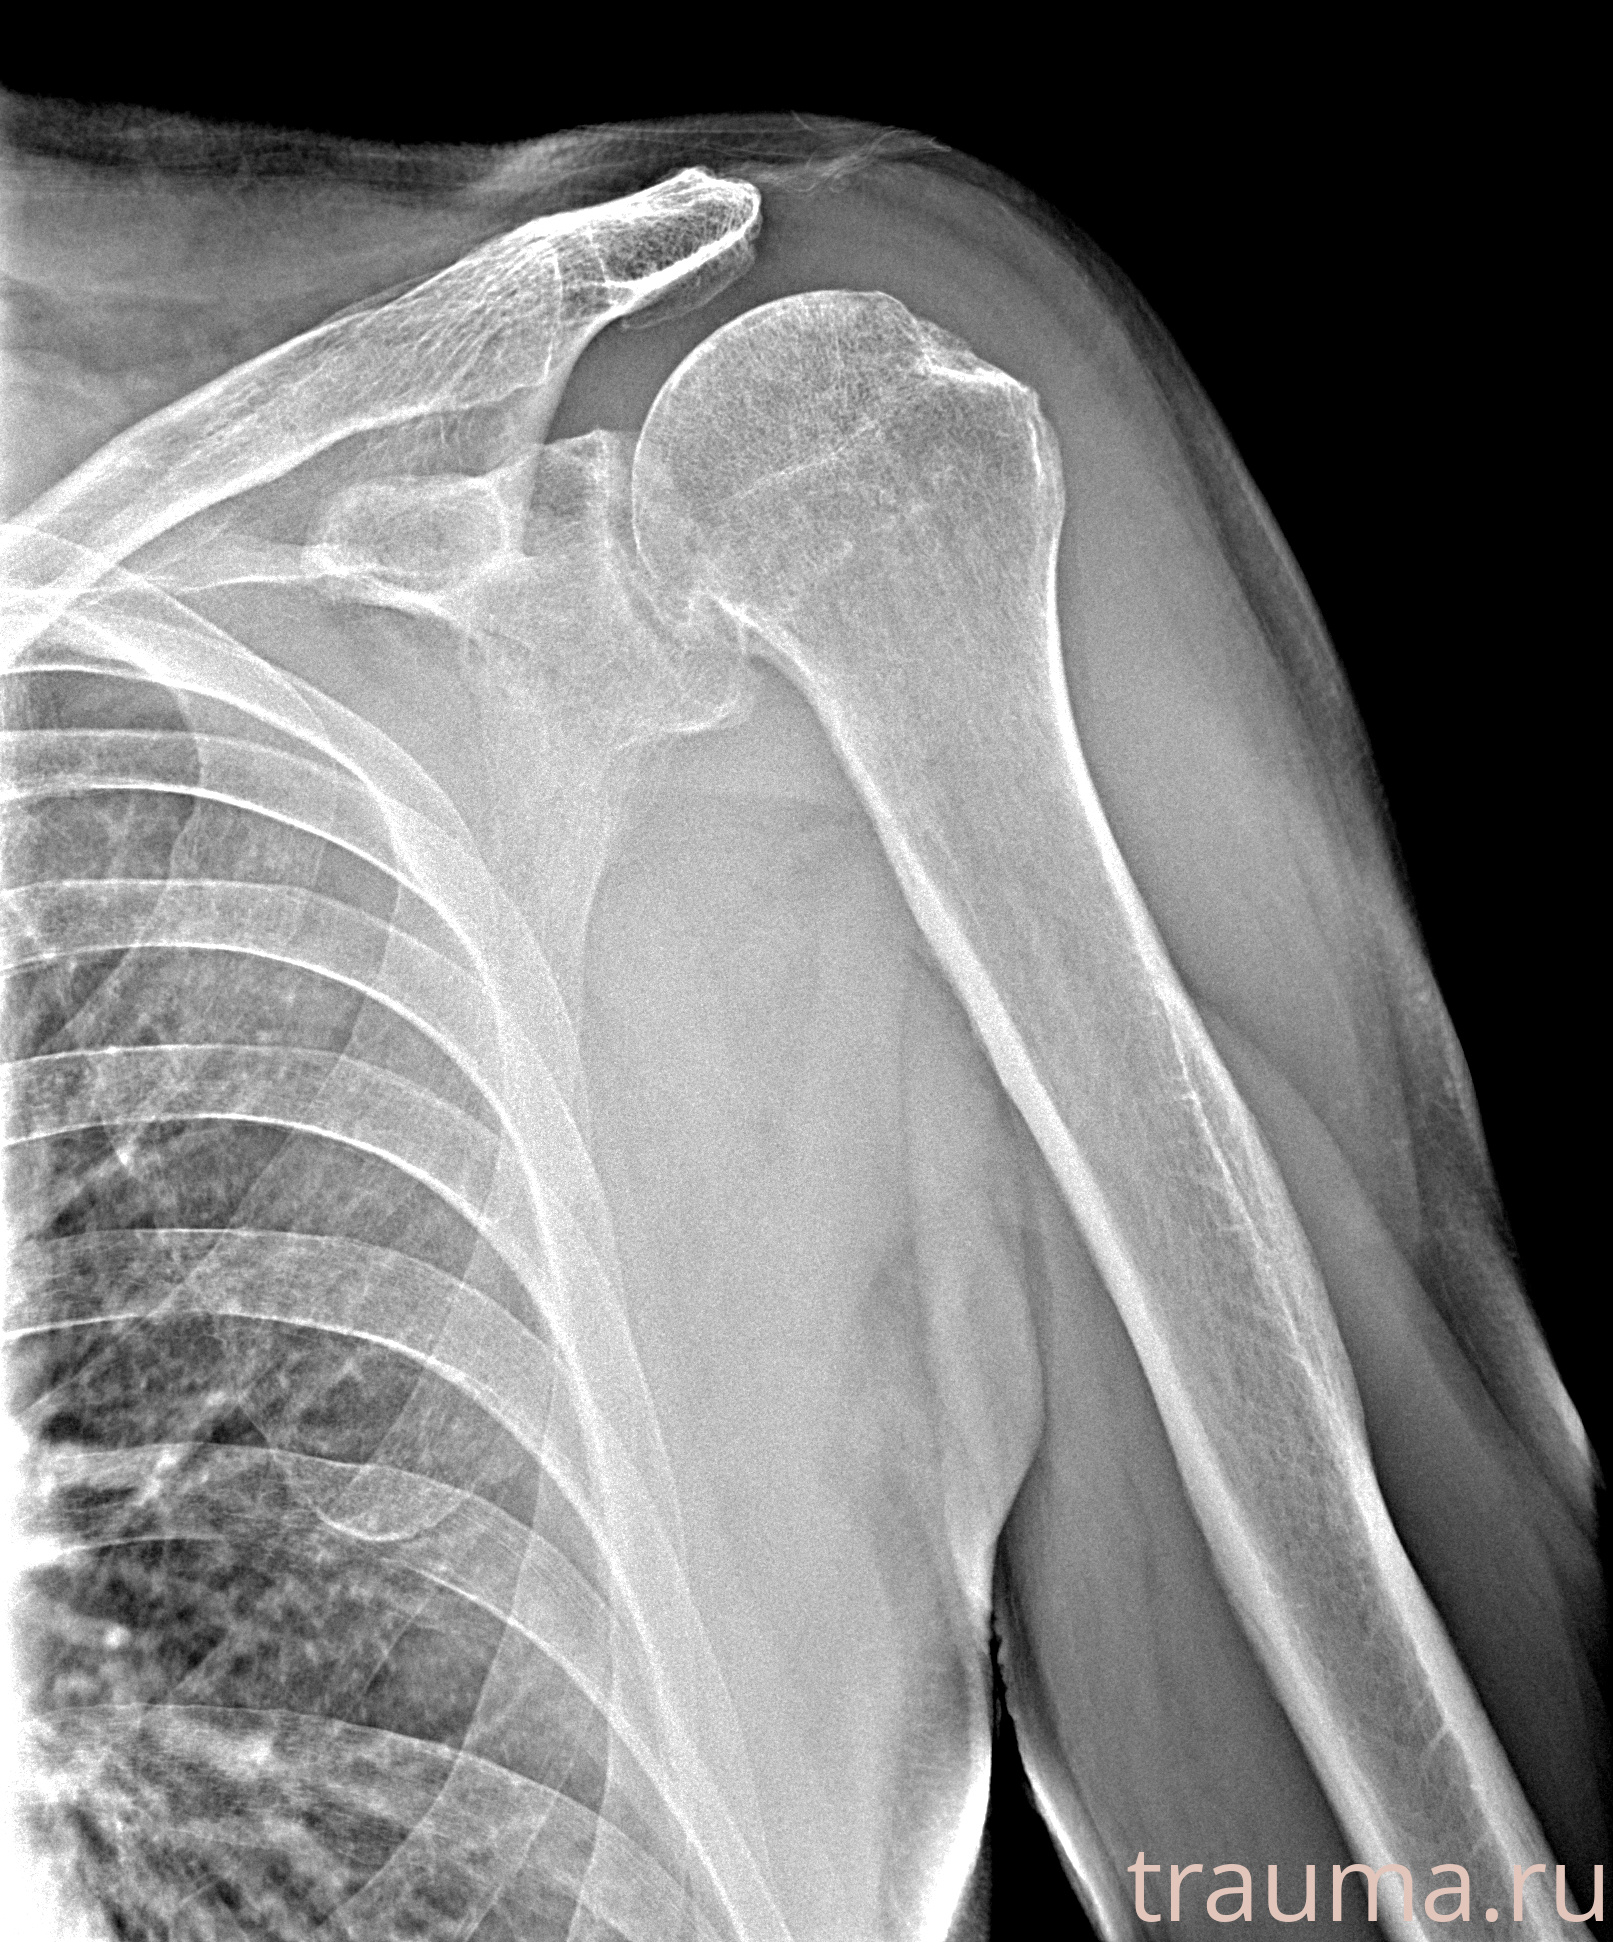

Рентгенограммы

Рентген на дому: по вашему адресу приезжает врач-рентгенолог, травматолог-ортопед с мобильным рентгеновским аппаратом, проводит диагностику травмы или заболевания, делает необходимые рентгенограммы, дает рекомендации по дальнейшему лечению. Получить качественные снимки в домашних условиях возможно благодаря уникальной методике, разработанной МосРентген Центром для института  Склифосовского